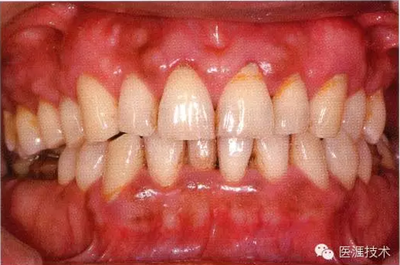

26歲男性牙齦炎的臨床圖像

26歲男性。開口呼吸。混合有牙齦發(fā)紅、腫脹與纖維性肥厚。菌斑干燥牢牢黏住,刷牙難以刷掉。